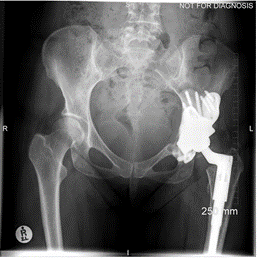

This case involves a 67-year-old gentleman who faced a series of complications due to hip trauma he had experienced over 50 years ago. After his primary and revision surgeries, and subsequent three hip replacements, he was left with a failing hip implant. His most recent hip replacement lasted 13 years before massive circumferential acetabular osteolysis caused the cup to loosen. Imaging revealed anterior and medial wall deficiencies, while the posterior column remained intact. The patient had a metal-on-polyethylene (MoP) bearing, which over time led to the wear of the polyethylene liner, triggering an inflammatory reaction and bone loss due to polyethylene debris.

The surgical plan required a custom 3D-printed acetabular cup, designed specifically for the patient's anatomy. The implant was designed with three flanges for optimal fixation. The surgery involved a posterior approach, with meticulous bone preparation to minimize further bone loss and ensure the custom implant fit securely.

This case represents ALTR with MoP. ALTR was characterized by massive osteolysis of the pelvic bone, which was most likely caused by polyethylene wear debris. This case underscores the complexity of revision hip surgeries and highlights the value of custom 3D-printed implants for achieving secure fixation and improving patient outcomes despite significant bone loss. Update at 7 years post operative is that the patient has excellent hip function and more can be seen in this paper: